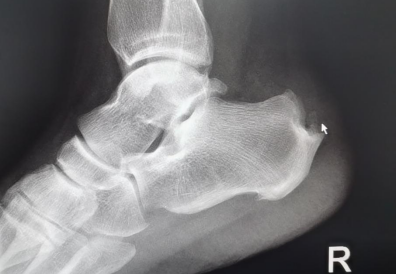

“經(jīng)X光、磁共振等詳細(xì)檢查,提示患者雙側(cè)跟骨結(jié)節(jié)增生、跟腱有變性,雙側(cè)跟骨結(jié)節(jié)區(qū)域及跟腱止點(diǎn)表現(xiàn):組織充血、水腫,結(jié)合病情及查體,考慮跟骨骨性突起畸形,經(jīng)診斷,為Haglund綜合癥(止點(diǎn)性跟腱炎、跟骨后上突增生與跟腱滑囊炎的統(tǒng)稱)。”李彬主任表示,該病癥主要表現(xiàn)為跟腱止點(diǎn)部位疼痛不適,運(yùn)動(dòng)時(shí)疼痛加??;或者清晨起床后出現(xiàn)疼痛,漸進(jìn)性病程發(fā)展,后期疼痛加重,影響生活質(zhì)量。